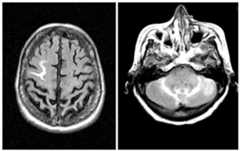

Figure 2.

ARIA-E detected on FLAIR images from a monoclonal antibody trial study demonstrating increased MR signal in sulci, thought to represent proteinaceous fluid tracking in the leptomeninges and sulcal spaces.

In some cases, the increased MR signal is primarily seen in what appears to be the leptomeningeal space (seeFigure 2 below). This leptomeningeal involvement may be seen in isolation or near associated grey matter alterations. This focal increased signal has on occasion been misinterpreted as subarachnoid hemorrhage, but neither cerebrospinal fluid (CSF) studies nor susceptibility weighted imaging have revealed evidence of blood products in these cases. It remains unknown whether this increased signal in leptomeningeal compartments might represent other proteinaceous collections of fluid.